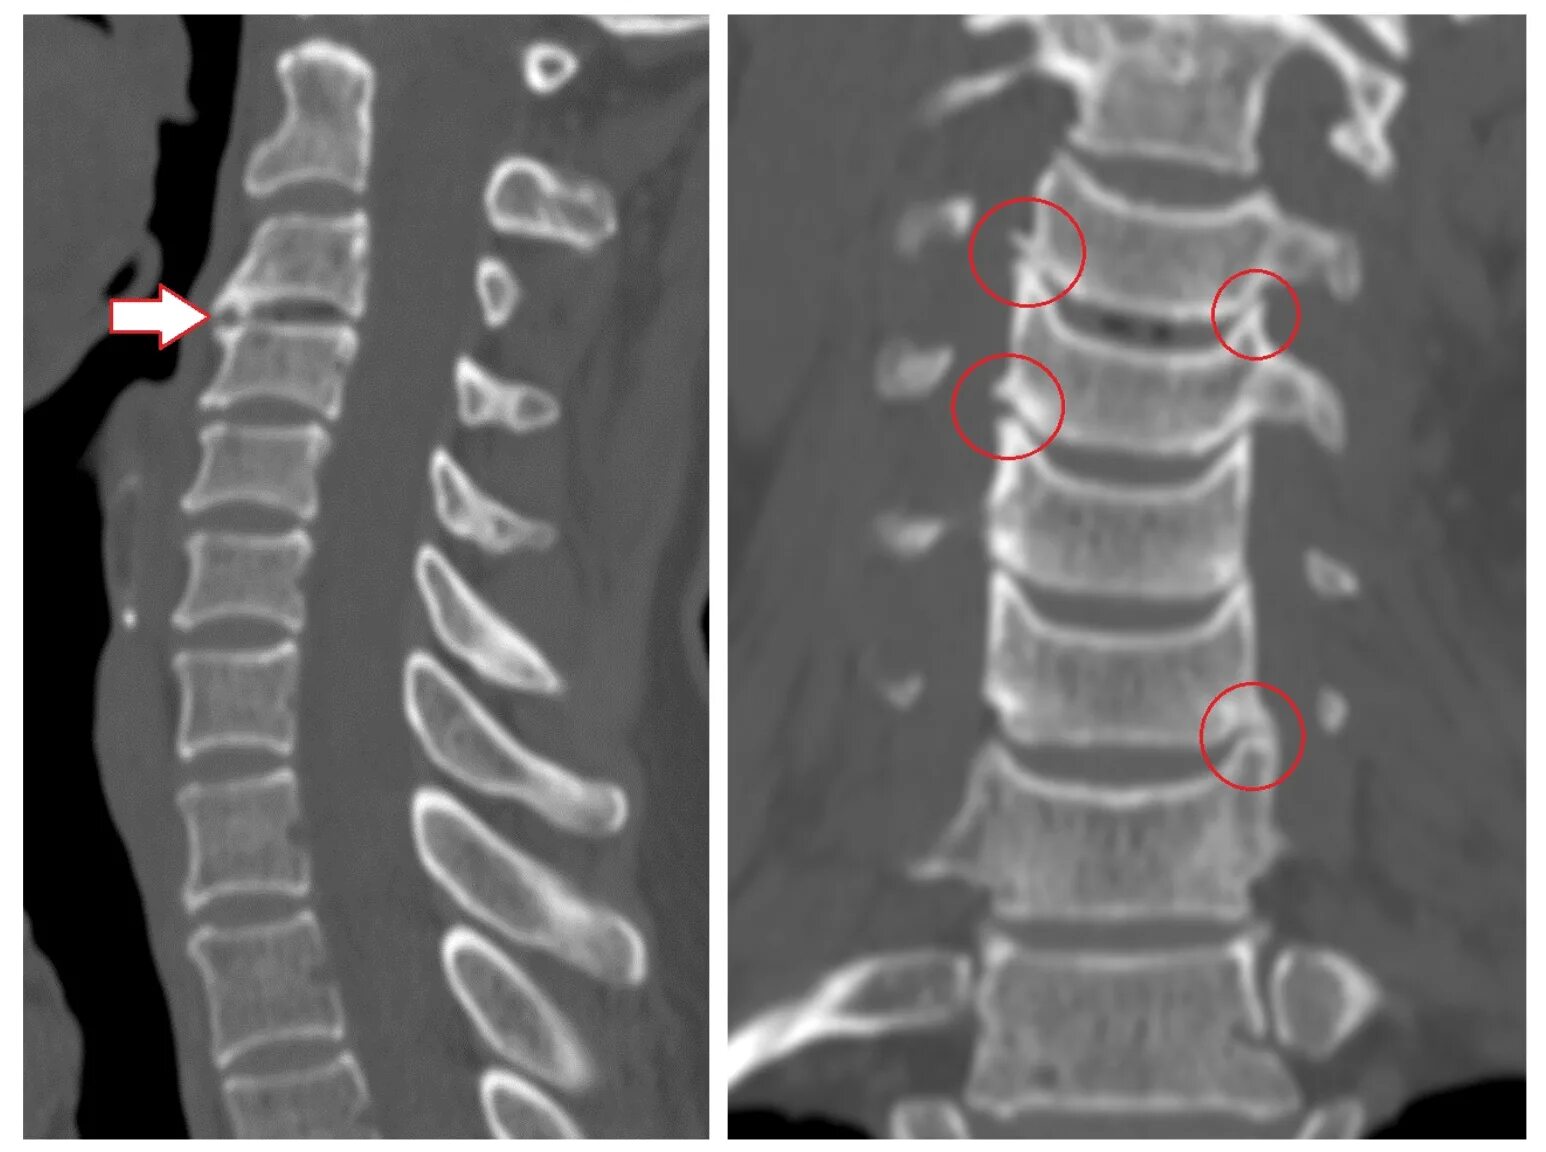

Сегмент с2 с3